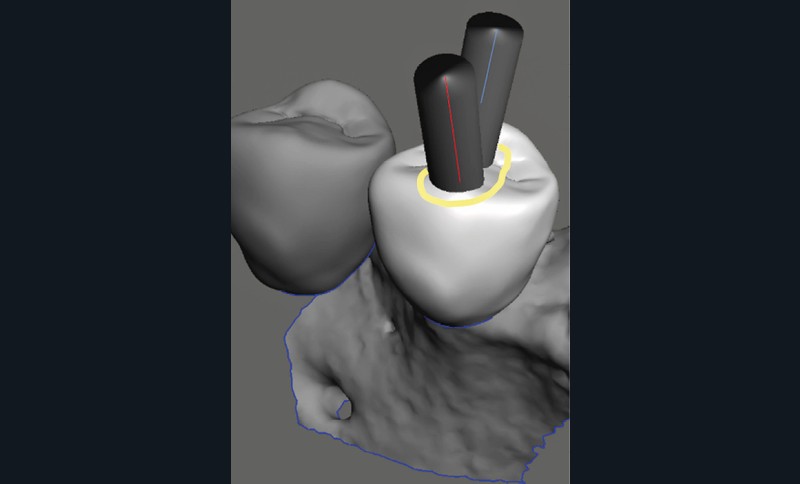

La cavité d’accès endodontique était alors traditionnellement réalisée en se figurant les axes de la racine et du bridge (fig. 2). Cette aptitude à s’orienter dans l’espace n’est cependant pas aisée, et différents outils numériques offrent aujourd’hui la possibilité de dessiner la trajectoire suspectée du canal sur les coupes de l’examen Cone Beam et d’aider le praticien à planifier son futur geste thérapeutique (fig. 3, 4). Après pose du champ opératoire, une voie d’accès est ainsi réalisée à travers le bridge en reportant les mesures de la planification 3D (fig. 5). Le tenon est déposé par vibration avec un insert ultrasonore puis la lecture des teintes dentinaires sous microscope permet d’objectiver la présence d’un canal supplémentaire non traité (fig. 6). Les surplombs dentinaires sont supprimés avec un insert ET18D (Actéon) et les entrées canalaires relocalisées avec une lime rotative d’évasement coronaire.